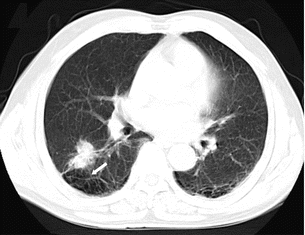

原发性肺肿瘤穿刺后发生小气胸

![]() |

胸膜间隙和叶间裂存在脏层胸膜,过肺叶间裂穿刺容易发生气胸。